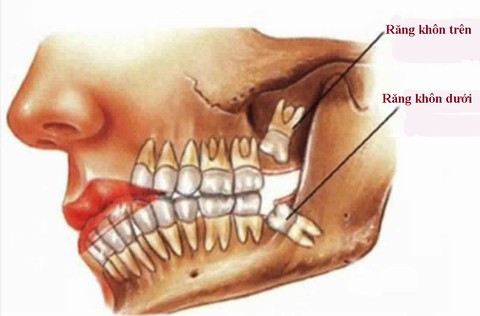

Theo các bác sĩ, răng số 8 (răng khôn) là chiếc răng mọc cuối cùng trên cung hàm. Chiếc răng này thường dễ bị mọc lệch, chèn ép các răng khác hoặc gây nhiễm trùng, đau nhức nên đôi khi nha sĩ thường khuyên nhổ bỏ.

- Răng khôn mọc lệch, mọc sai vị trí thường kèm theo các triệu chứng sưng lợi, nướu, đau buốt và cứng hàm do răng không đủ khoảng trống để mọc lên nên bị kẹt một phần hoặc toàn bộ trong xương hàm.

- Răng số 8 bị mọc kẹt dễ gây bệnh lý lợi trùm.

- Khi mọc kẹt, lợi trùm, thức ăn bị đọng lại góc lợi khó được lấy ra nên dễ gây sâu răng hàm số 7.

- Vùng lợi trùm xung quanh răng khôn dễ bị sưng đau, nhiễm trùng do thức ăn giắt vào khó được lấy ra dễ gây sưng đau, nhiễm trùng.

- Nếu răng khôn mọc ngang, mọc lệch cũng sẽ đâm vào răng hàm ở phía trước, gây ra nhiều biến chứng cho răng miệng.

- Chỉ khi mọc răng khôn mọc ngầm, mọc lệch, đâm vào răng số 7 gây đau nhức, ê buốt kéo dài thì nha sĩ mới chỉ định nhổ răng số 8.

- Nhổ răng khôn mọc lệch cần được thực hiện bởi nha sĩ giàu kinh nghiệm vì rất dễ gây các biến chứng, nhất là khi răng số 8 có vị trí mọc đặc biệt, khó điều trị.